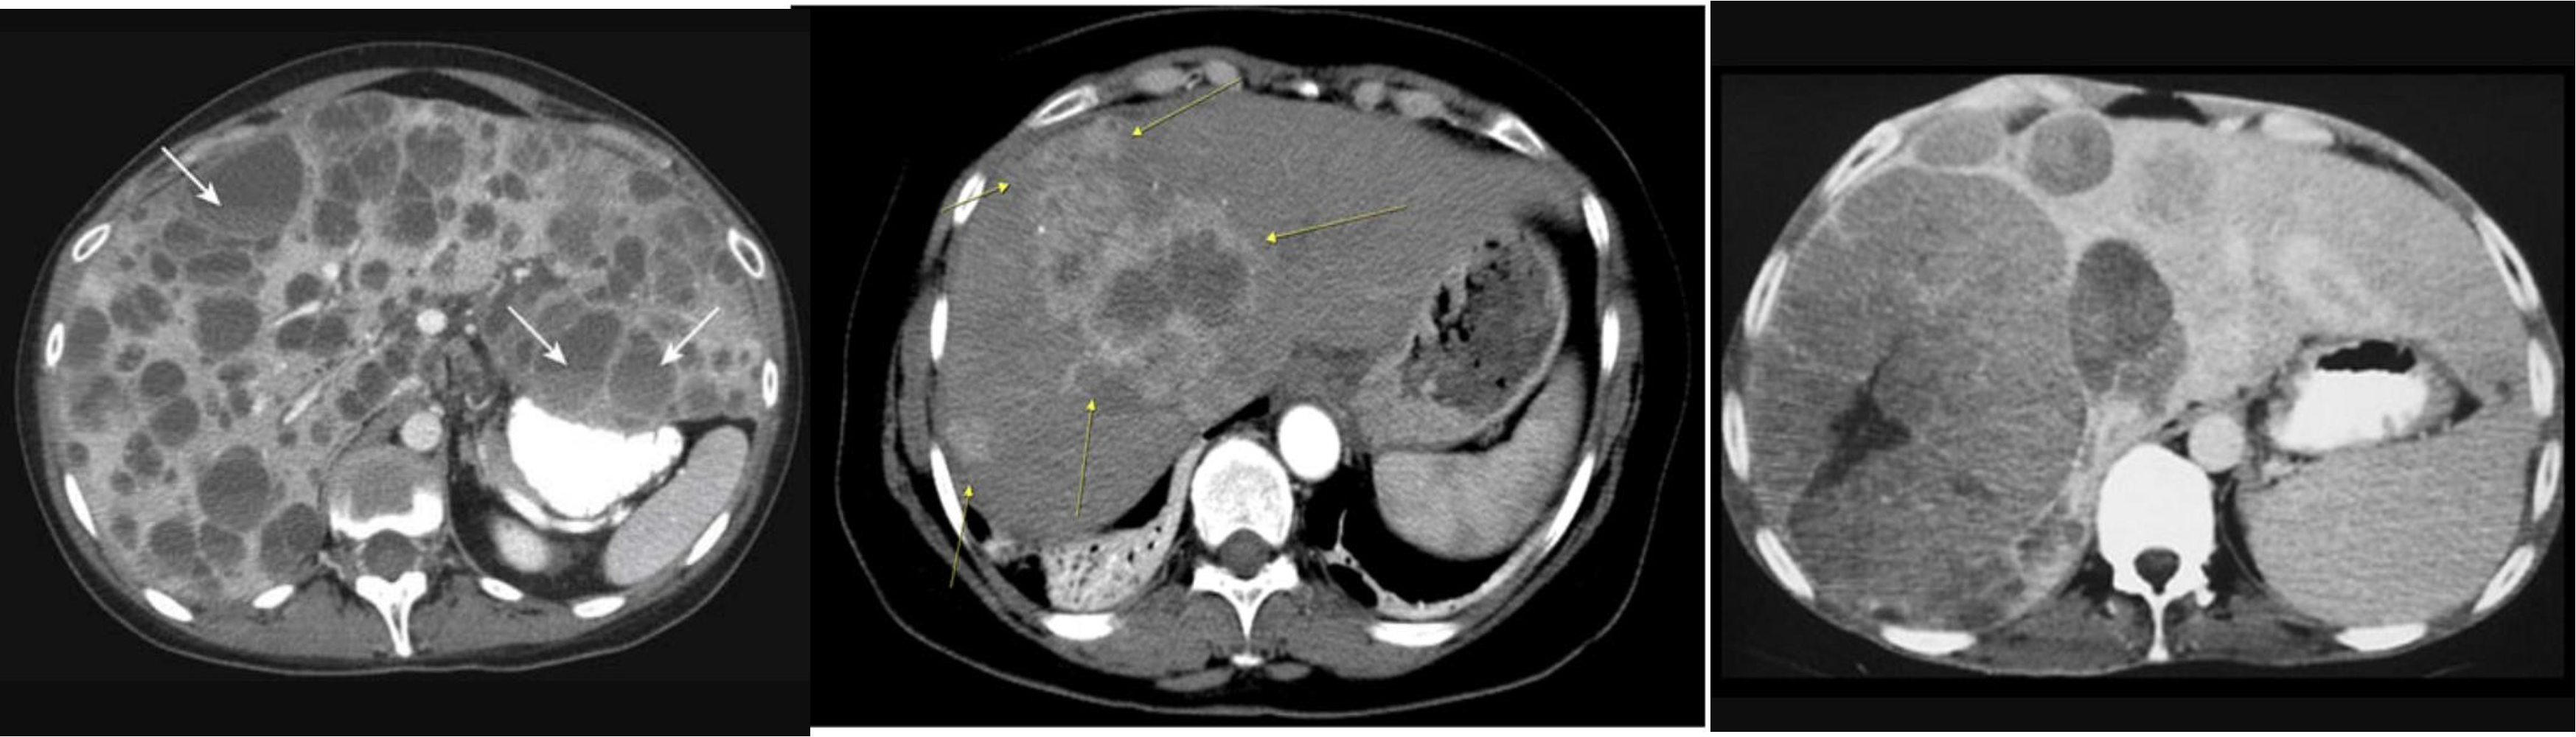

- CBD + METASTESIS

- hypodense - spleenomegaly with splenic infarct

- patient compl anemia vomit - mass stomach - adenocarcinoma - stage 4 gastric cancer (cannon ball sign) - ct scan contrast porta

multiple lesion in liver due (Diff; cancer, multiple abcess pyogenic most likely)

Ireggular lesion peripheral enhancement - hypo in cent - febrile tender (liver abcess) - antibiotic + ct u/s guidance drainage

HCC, Cancer of liver, hepatic adenoma, FNH (with central scar star like)

- ct scan (hypodense lesion in liver well circumscribed single - most likely amoebic liver abcess)

- multiple … metastasis